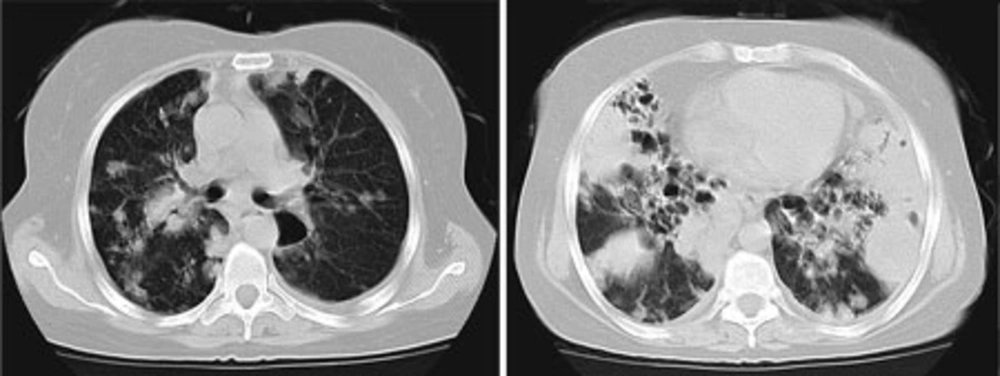

On arrival in emergency room, she appeared severely ill and she was in respiratory distress; respiratory rate 40 breaths/min, heart rate 120 beats/min, temperature 37.6° C, blood pressure 105/80 mm/Hg, and oxygen saturation 93% (with 4 litres of mask oxygen). Facial flushing, oral thrush and musical lung sounds were the remarkable findings. Further investigation revealed leukocytosis (white blood cells: 17 700/mm3), anemia (hemoglobin: 10.3 gr/dL), normal renal and liver function tests, elevated ESR (110 mm/hr), elevated serum lactate dehydrogenase (LDH) (1 190 U/L), and high random blood sugar (336 mg/dL). Mild proteinuria and glycosuria without pyuria, hematuria and casts were reported in the urinalysis. Chest roentgenogram showed multilobar infiltrates and also bronchiectasis, particularly in both of the upper lobes. She was commenced on azithromycin (500 mg loading dose, then 250 mg daily), piperacillin-tazobactam (4.5 gr q6h), bronchodilator, and hydrocortisone (50 mg q3h). Her chest computed tomographic (CT) scan is shown in Figure 1.